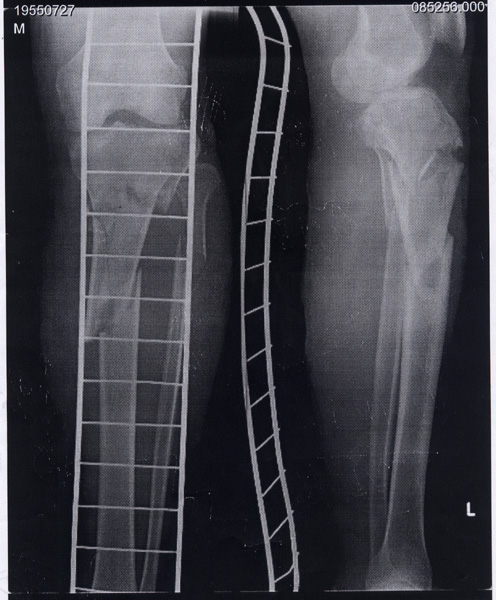

骨折 骨折倶楽部入部希望者に告ぐ。まず骨折とはこういうものです(白い梯子のような物は足の裏側に当てられたシーネです)。脛骨が3分割して内側に折れ曲がって、もちろん腓骨もポッキリ。

そして全身麻酔での手術、20cm程の金具を埋められ、ボルト…って言うか木ネジみたいなの11本打たれた(ちなみに腓骨は無視)。4秒で眠ってしまったので痛くは無かったが、病室へ戻ってから一晩気持ち悪かった。ち○ち○に管入れられていて、それ抜く時、思わず「痛ててててて…」と叫んでしまった。

手術 3月19日、事故、そして即日入院。病状、左脛骨近位端粉砕骨折及び腓骨骨折、左腓骨神経麻痺。

4月10日、やっと手術。全麻下観血的整復内固定術(Mizuho J-plate固定)。

入院から手術まで3週間掛かったのは、外傷はまったく無かったものの、最初の一晩にて膝下がパンパンに浮腫み、一面水泡が出来てしまった為だ。つまり、皮膚が壊死し、その再生に3週間掛かった。骨が付くのが早いか皮膚が直るのが早いか…、見舞いで頂いた小魚類やカルシウム剤もおあずけ、なにしろこのまま骨が付かれたら困る。大きく折れた所はともかく、関節部はちゃんと起こして貰わないと、ほんとうに歩けなくなる。手術は嫌だけど、このままくっ付いたのではもっと嫌だった。